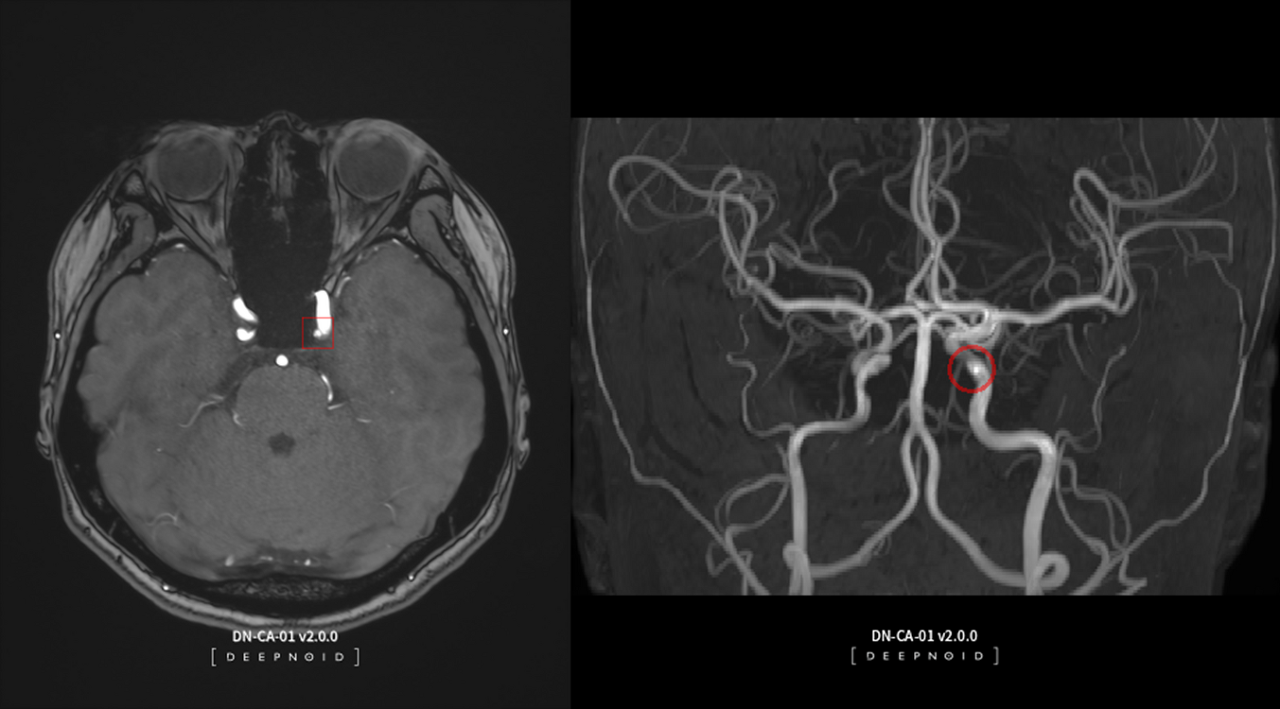

딥뉴로는 뇌 MRA 영상을 활용한 AI 기반의 뇌동맥류 검출 진단보조 솔루션으로 혁신의료기술이다.